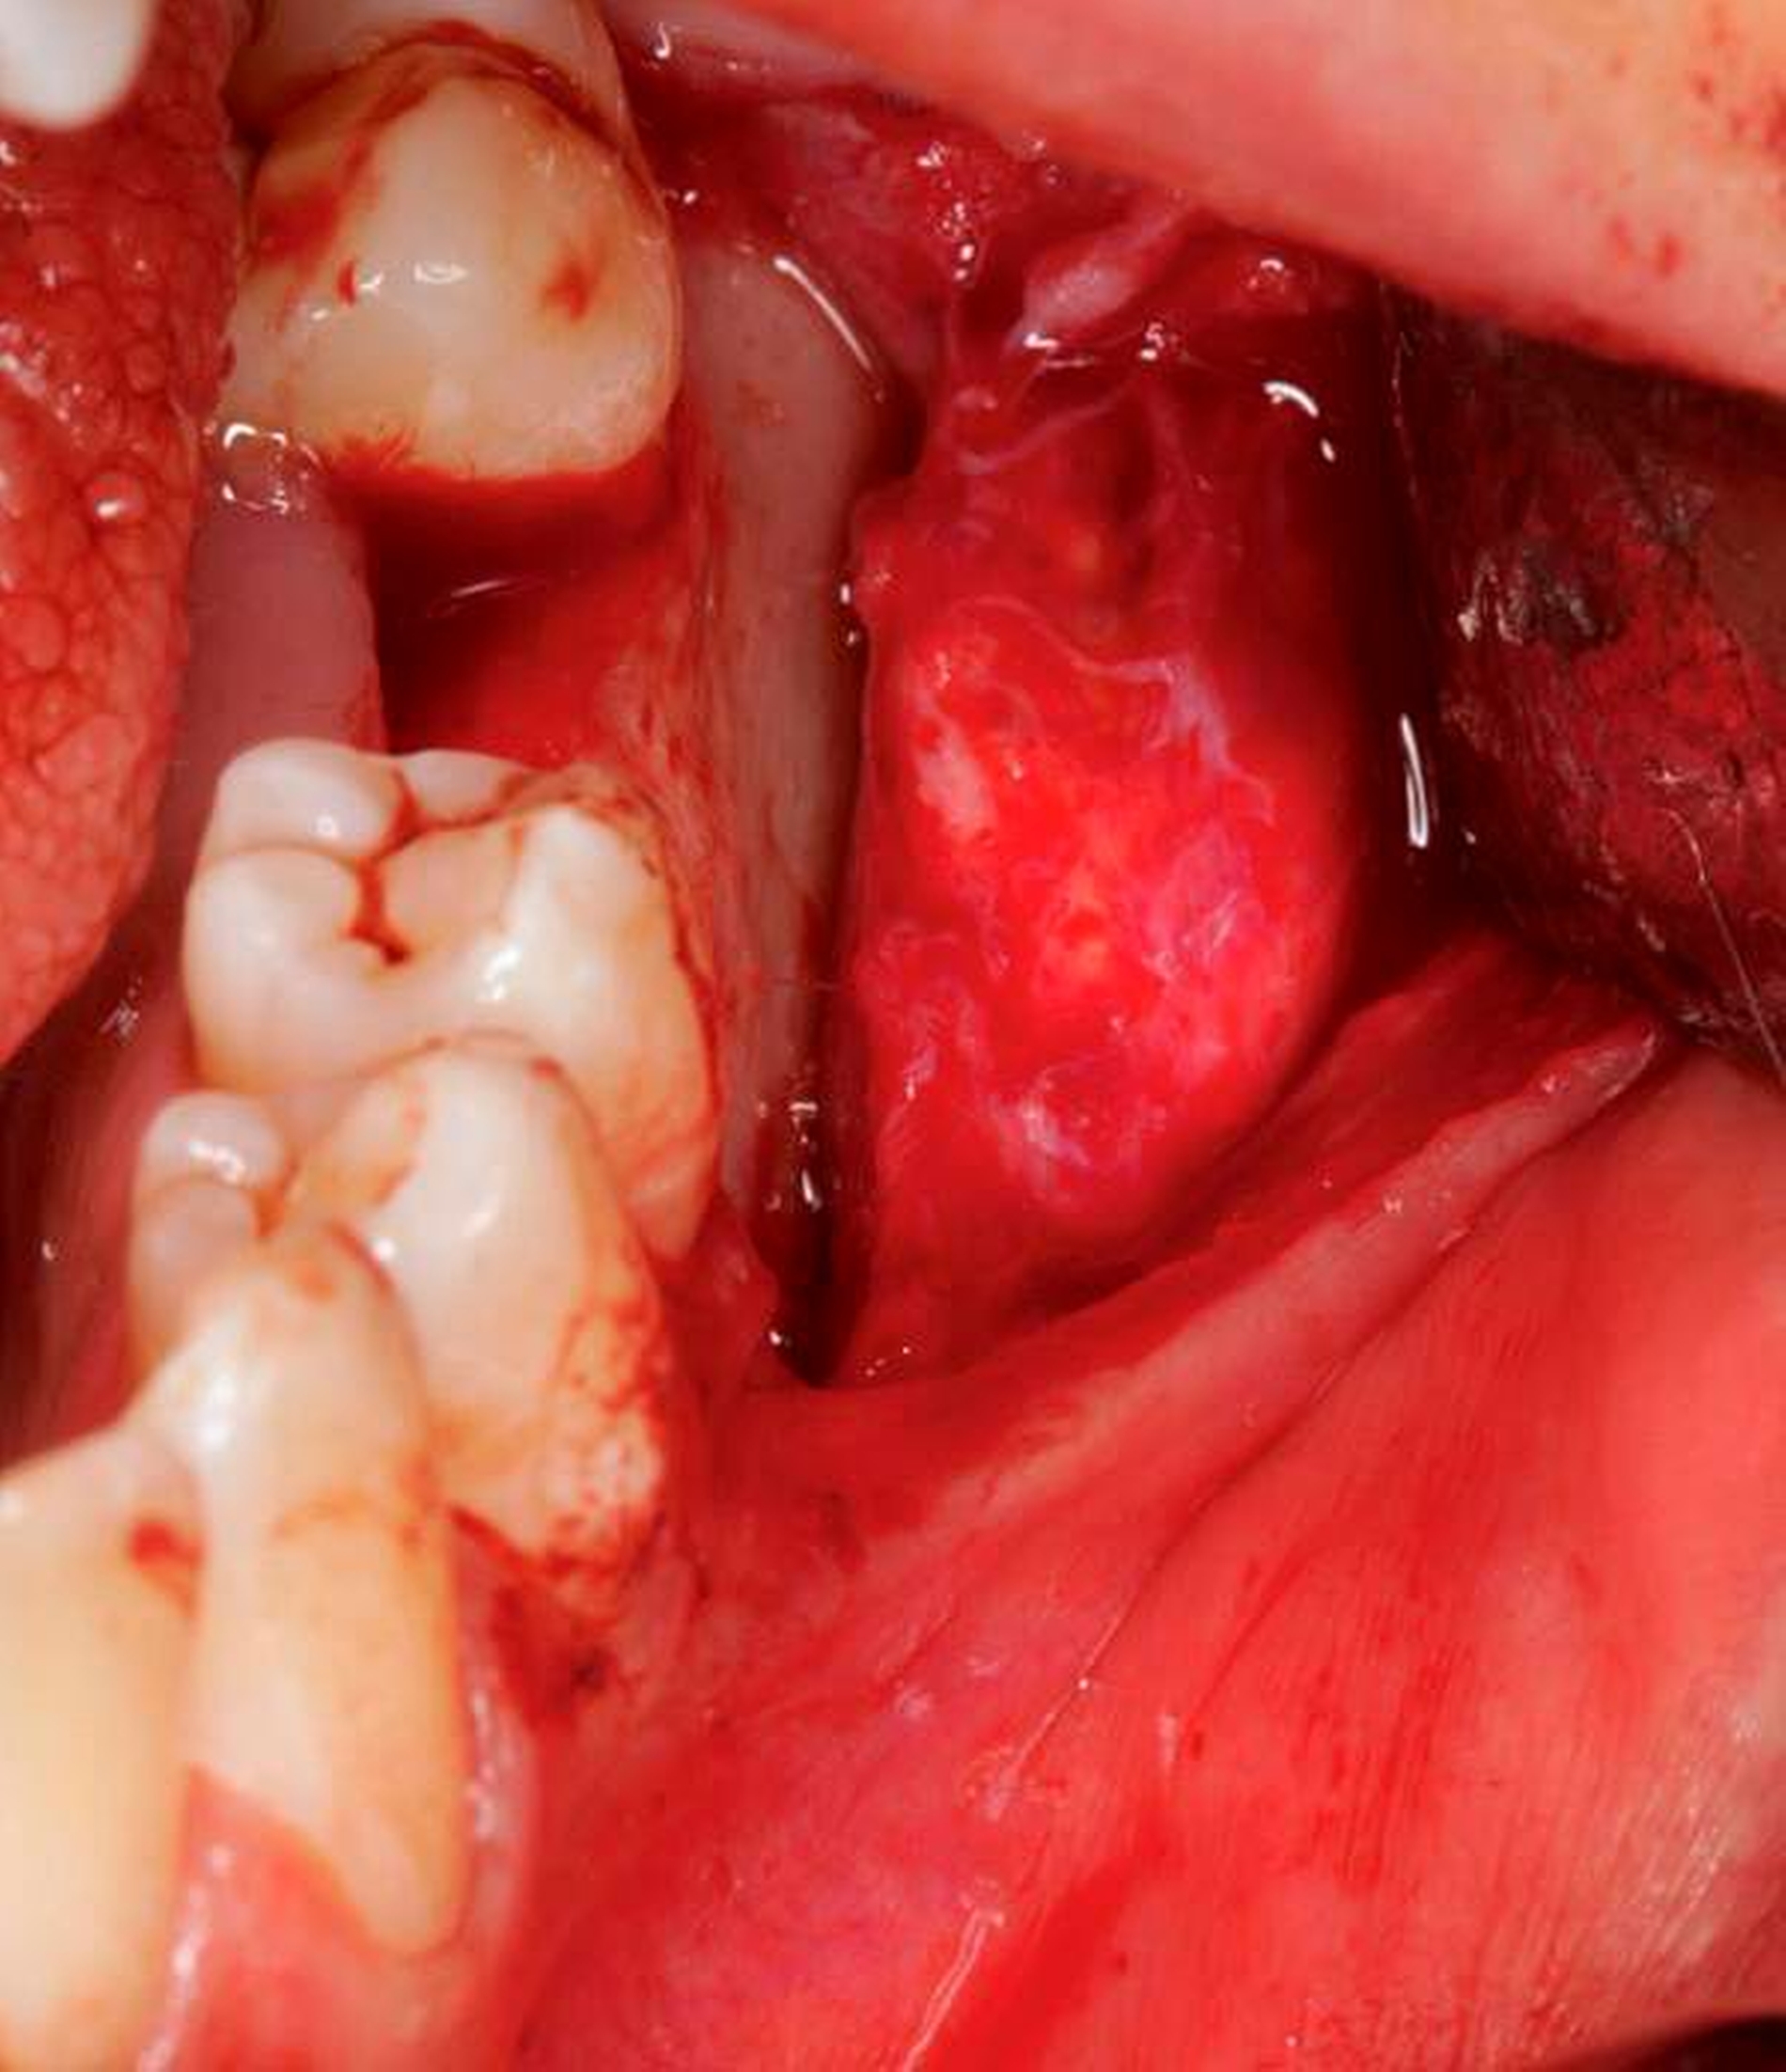

Auch radiologisch ließen sich keine Auffälligkeiten darstellen (Abbildung 1). Aufgrund der lang anhaltenden Persistenz und auf Wunsch der Patientin entschieden wir uns für eine chirurgische Inspektion mit Option auf Entfernung des Tumors. Analog zur Schnittführung der Weisheitszahnentfernung wurde das Gewebe Regio 36 marginal mit einer mesialen und distalen Entlastung eröffnet und ein Spaltlappen gebildet. Bis zur verdächtigen Raumforderung wurde stumpf mit der Schere präpariert (Abbildung 2), wobei sich die Läsion schließlich als abgekapselte Struktur darstellte, die sich sehr gut aus dem umliegenden Gewebe entfernen ließ. Das klinische Erscheinungsbild der Raumforderung entsprach am ehesten der eines Lipoms (Abbildung 3). Nach kompletter Entfernung der Raumforderung (Abbildung 4) wurde die Wunde mit Nähten speicheldicht verschlossen (Abbildung 5).